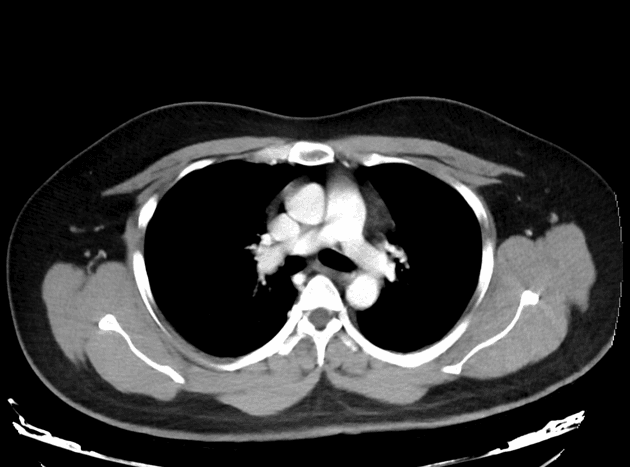

Giải phẫu bình thường của động mạch mạc treo tràng trên...

Giải phẫu bình thường của động mạch mạc treo tràng trên để đối chiếu.

Các hình ảnh có chú thích làm rõ động mạch mạc treo tràng trên và các nhánh của nó trong một trường hợp bình thường khác để so sánh.